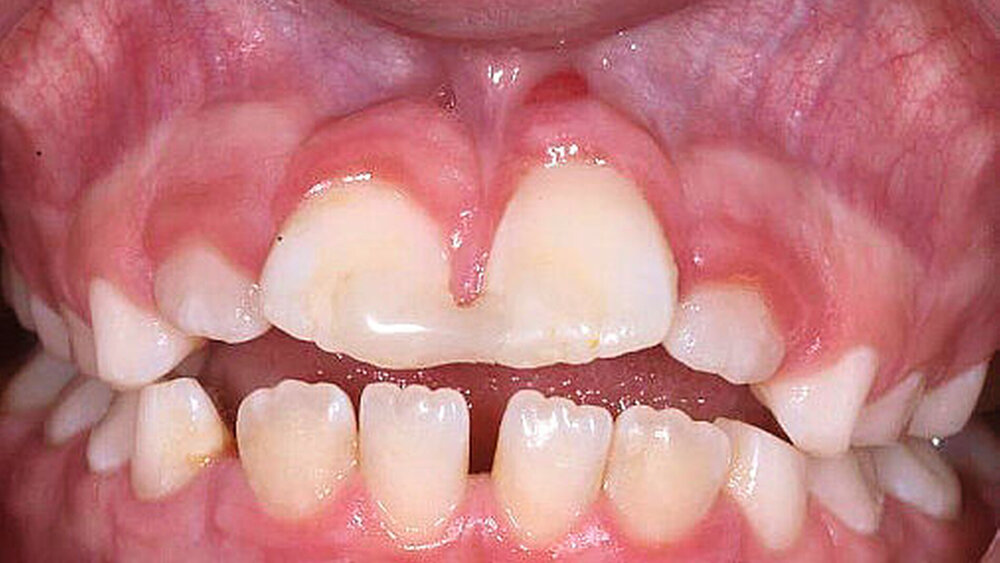

Die dargestellten Behandlungsempfehlungen sollen nun – zuerst am klinischen Fall eines elfjährigen Mädchens – reflektiert werden (Abbildung 3): Die anamnestische Angabe einer Trockenlagerungszeit des avulsierten Zahnes von rund 60 Minuten muss als extrem ungünstig für die Langzeitprognose des Zahnes angesehen werden. Die Replantation des Zahnes durch den Hauszahnarzt war trotz dieser Lagerungsbedingungen völlig richtig. Lediglich die nach folgende Therapie (Schienungsart: rigide; Schienungszeit: zwei Jahre; keine weiteren Röntgenkontrollen und damit auch keine Wurzelkanalbehandlung nach ersten Anzeichen einer Wurzelresorption) entspricht nicht den Anforderungen an eine adäquate posttraumatische Nachsorge. Daraus ergeben sich sekundäre Probleme für das weitere Kieferwachstum (posttraumatische Ankylose), die im Folgenden besprochen werden.

Umgang mit primären und sekundären Verlusten: Die Therapie der posttraumatischen Ankylose im jugendlichen Gebiss stellt eine der schwierigsten therapeutischen Aufgaben dar. Mittelfristig kommt es zum vorhersagbaren Zahnverlust bedingt durch fortschreitende Wurzelresorption (sekundärer Verlust).